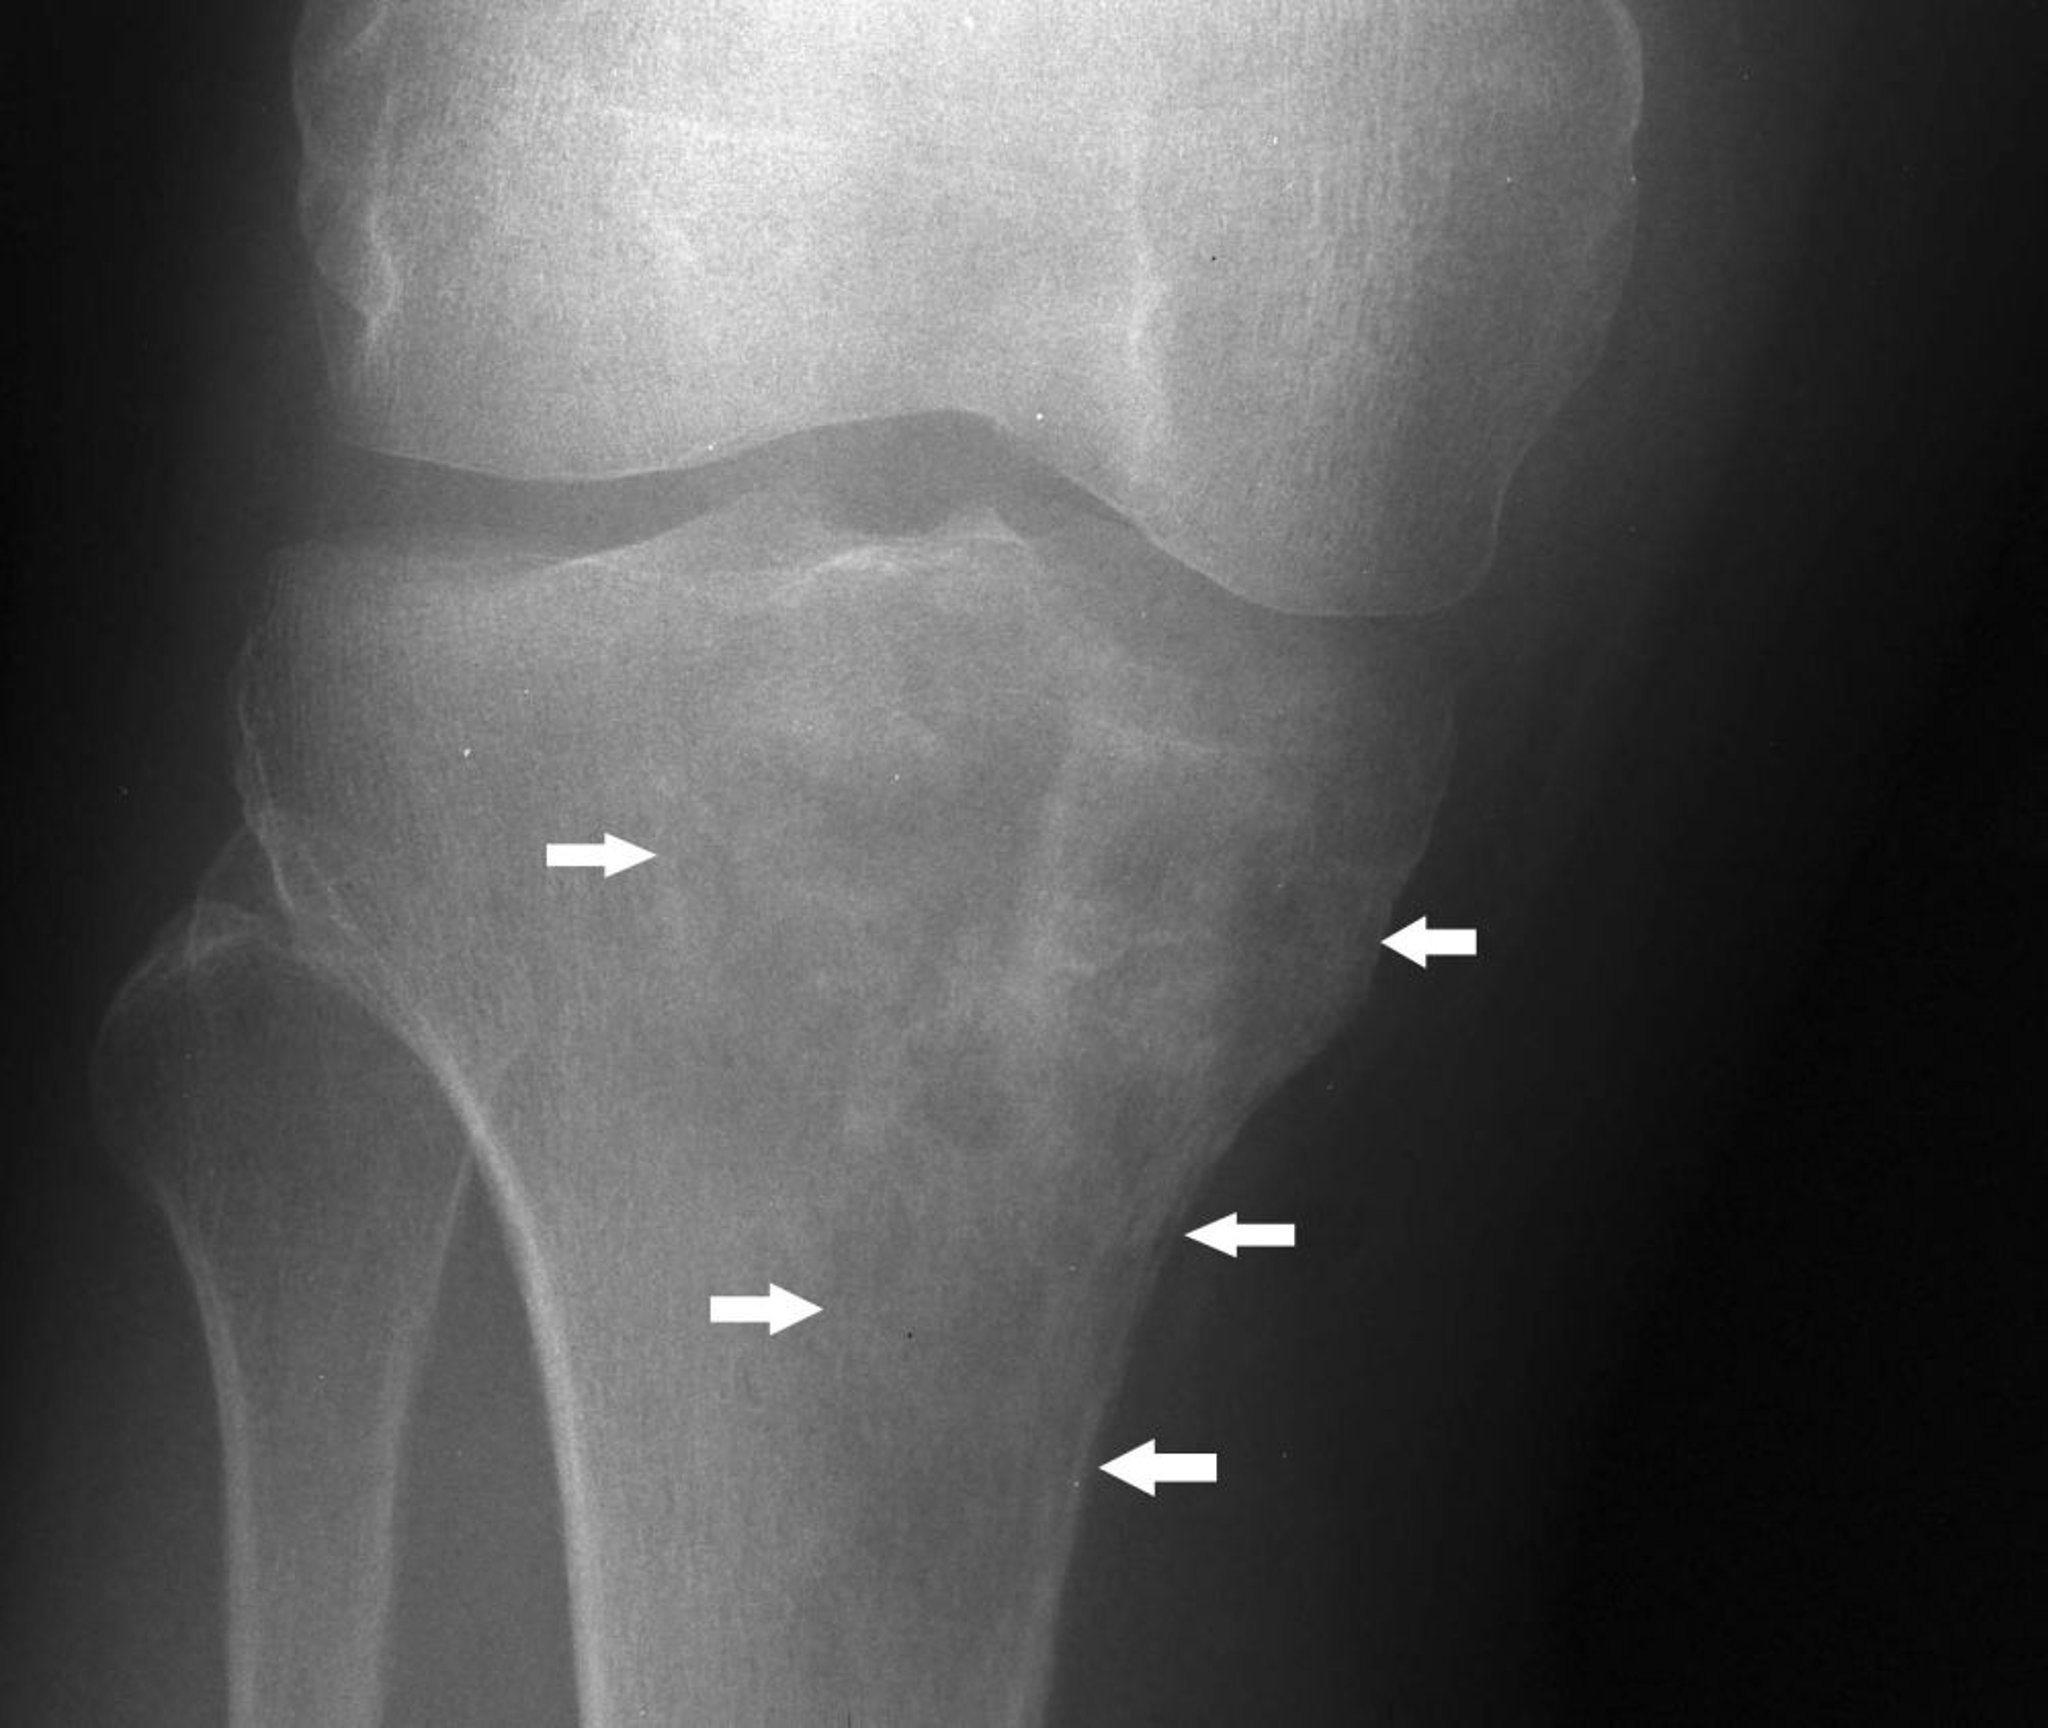

Questa radiografia del ginocchio mostra un linfoma nella tibia prossimale con un aspetto misto litico e sclerotico sotto il condilo tibiale mediale (frecce).

Image courtesy of Michael J. Joyce, MD, and Hakan Ilaslan, MD.